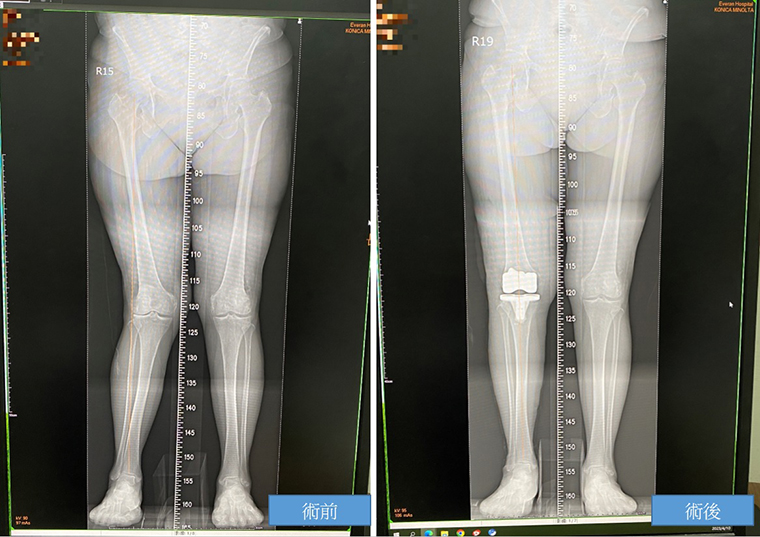

▲患者術前術後對照圖。(圖/長安醫院提供)

【NOW健康 陳郁茹/台中報導】70歲的巫女士年輕時右腳膝蓋曾受傷但未治療,隨著年齡增長,她的右腳出現X型腿,走路也一跛一跛的。近1、2年來,她的疼痛明顯惡化,已經嚴重影響到正常生活。她前往長安醫院骨科求診,經檢查發現可能是右膝韌帶長期受傷沒有處理所致,導致右膝外側退化嚴重。經人工膝關節置換手術後,巫女士的右腳X型矯正變直了,疼痛和步態也都得到了顯著的改善。

針對患者的治療情況,醫生進行了全人工膝關節置換手術,除了矯正膝蓋歪斜的角度外,還切除了軟骨和骨頭磨損的部分,提供新的關節界面,以改善步態和緩解疼痛。手術後的隔天,巫女士已能下床行走,開始進行復健訓練。1個月後的回診,她的行走姿勢已恢復正常,可以不需要使用拐杖,讓她非常欣喜。